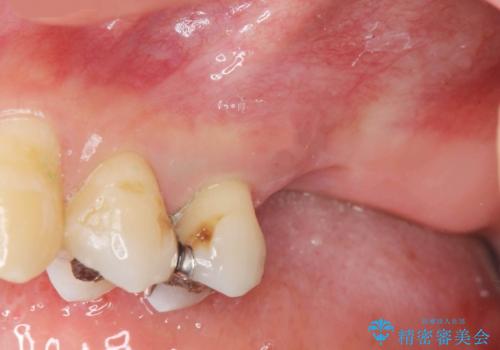

上顎奥歯のインプラント治療

- 奥歯を失い咬合機能の回復のためインプラント治療を希望され来院されました。

奥歯を2本失うと、他の歯の負担が増加し残っている歯の状態が悪くなるリスクがあります。

しっかりと咬合機能の回復できるインプラント治療を計画します。